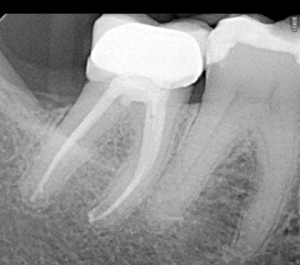

Clinical Cases